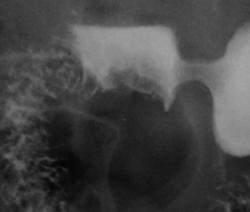

Ой Валентин Львович, с вашего разрешения хотел бы продемонстрировать рак желудка, но другую форму,  со значительным распрастранением:

Пациентка попала ко мне после проведения ФГДС, эндоскописты толком не могла попасть в антральный отдел, гистологию взяли, а после скопии уже была про оперирована.

Жалобы у неё интересные; быстрая насыщаемость после не большого приёма пищи, визуально-очень худенькая.

Гистологически -злокачественный рост, более точную формулировку не вспомню, данная пациенка была месяца 2-3 назад, ей провели гастрэктомию, хирурги-онкологи в протоколе описали о наличие объёмного образования желудка,  с распрастранением во все отделы.

Не поняла вопрос, если про демонстрацию Виталия, то экзофитный рак желудка, субтотальное распространение